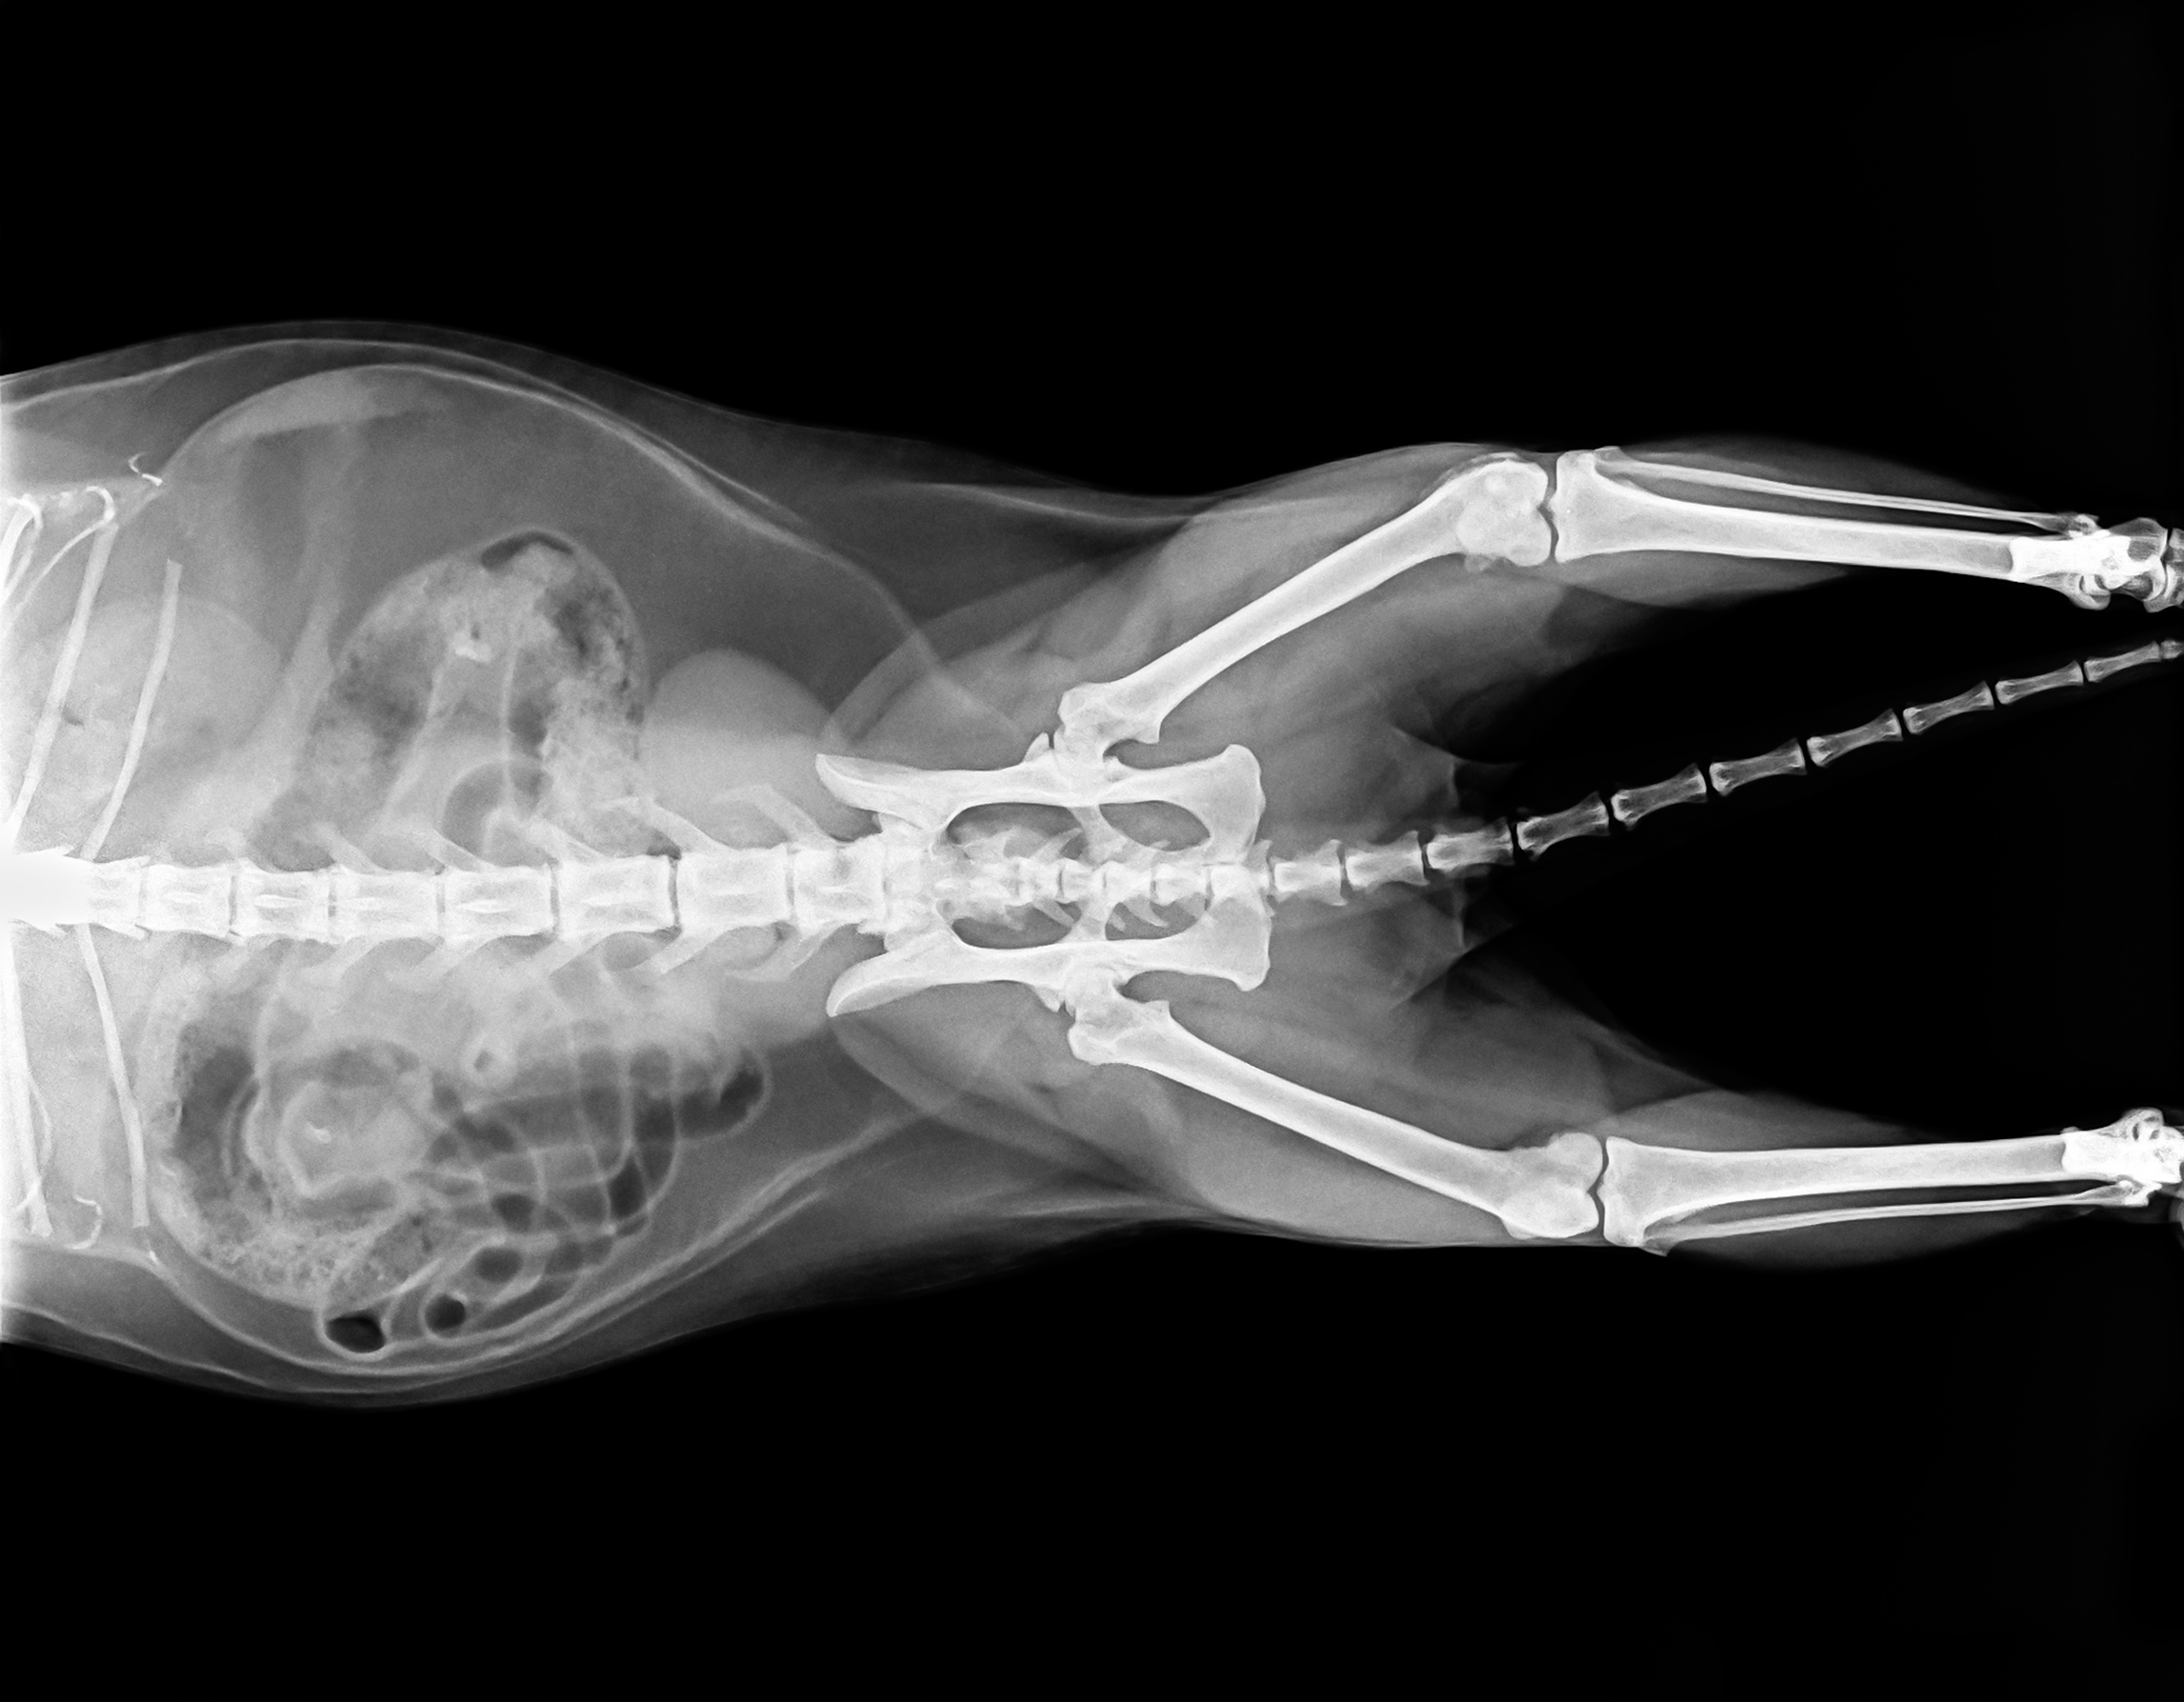

Рентген кошки фото - найдено 30 изображений